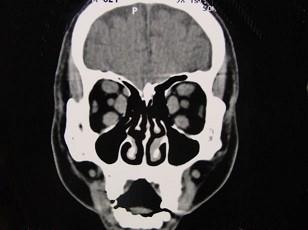

问题 女性50岁,消瘦、多饮多食,脖子粗大,双侧眼球突出,一年余,CT检查如图所示,应考虑为 ( )

选项 A、横纹肌肉瘤 B、眶部结核 C、甲状腺眼病 D、炎性假瘤 E、眼型格氏病

答案 C